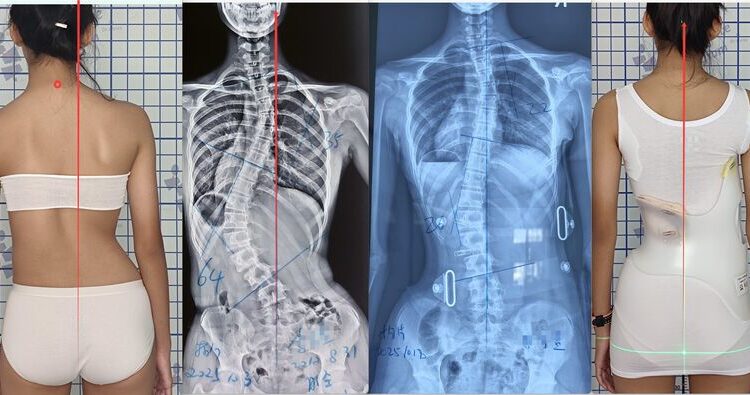

يعاني العديد من الأطفال والمراهقين من اعوجاج العمود الفقري مجهول السبب، وهو انحناء جانبي للعمود الفقري يظهر عادة في مرحلة النمو السريع قبل البلوغ. هذا الانحناء قد يبقى بسيطًا عند بعض الأطفال، بينما يزداد تدريجيًا عند آخرين. يطرح الأهل دائمًا أسئلة مهمة: هل يحتاج طفلي للعلاج؟ متى يكون استخدام حزام اعوجاج العمود الفقري كافيًا؟ ومتى تكون الجراحة ضرورية؟ في هذا المقال، سنجيب على هذه الأسئلة بطريقة سهلة وواضحة، مع التركيز على ما يهم الأهل والمراهقين.

يعني “المسار الطبيعي” تطور الانحناء دون تدخل علاجي. تشير الدراسات إلى أن معظم الانحناءات البسيطة، خاصةً إذا كانت زاوية كوب (Cobb Angle) أقل من 20 درجة، لا تتفاقم بشكل خطير. ومع ذلك، بعض الانحناءات قد تزداد تدريجيًا، خصوصًا إذا تجاوزت الزاوية 30 درجة خلال مرحلة النمو، أو 35 درجة أثناء طفرة النمو السريعة في سن المراهقة.

يُوصى باستخدامه إذا كانت زاوية كوب بين 25 و45 درجة والطفل لا يزال في مرحلة النمو.

تُفكر الجراحة عندما تتجاوز زاوية كوب 50 درجة أو إذا تسبب الانحناء في مشاكل صحية مثل صعوبة التنفس أو ألم شديد.

الجراحة الحديثة تعتمد على أنظمة متعددة من الخطاطيف (multi-hook systems) لتصحيح الانحناء في المستوى الأمامي-الخلفي (coronal plane). رغم ذلك، لا توجد بعد أنظمة قادرة على تصحيح الالتفاف الثلاثي الأبعاد بالكامل، لكن التطورات الحديثة تساعد على تقليل الانحناء بشكل ملحوظ وتحسين جودة الحياة.